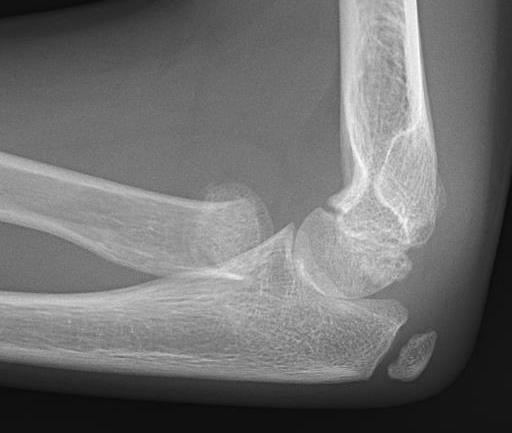

Radial neck fracture and olecranon fracture